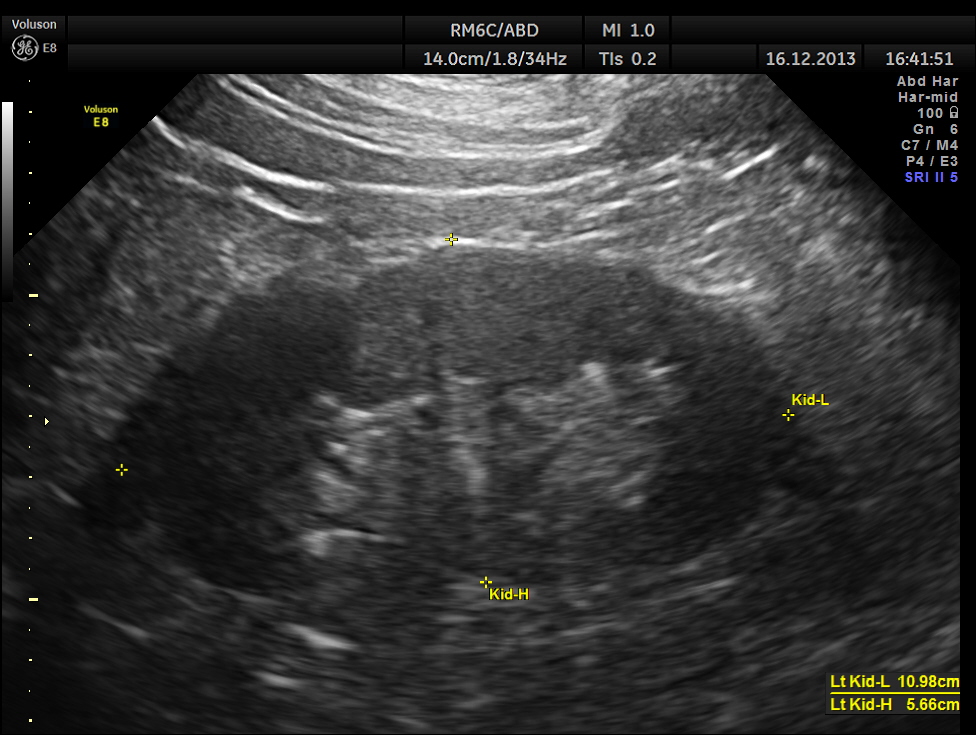

He also had mild prostatomegaly.